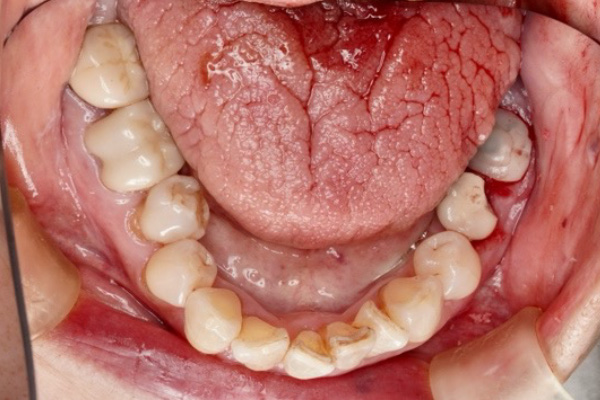

治療前(Before)

治療中の様子